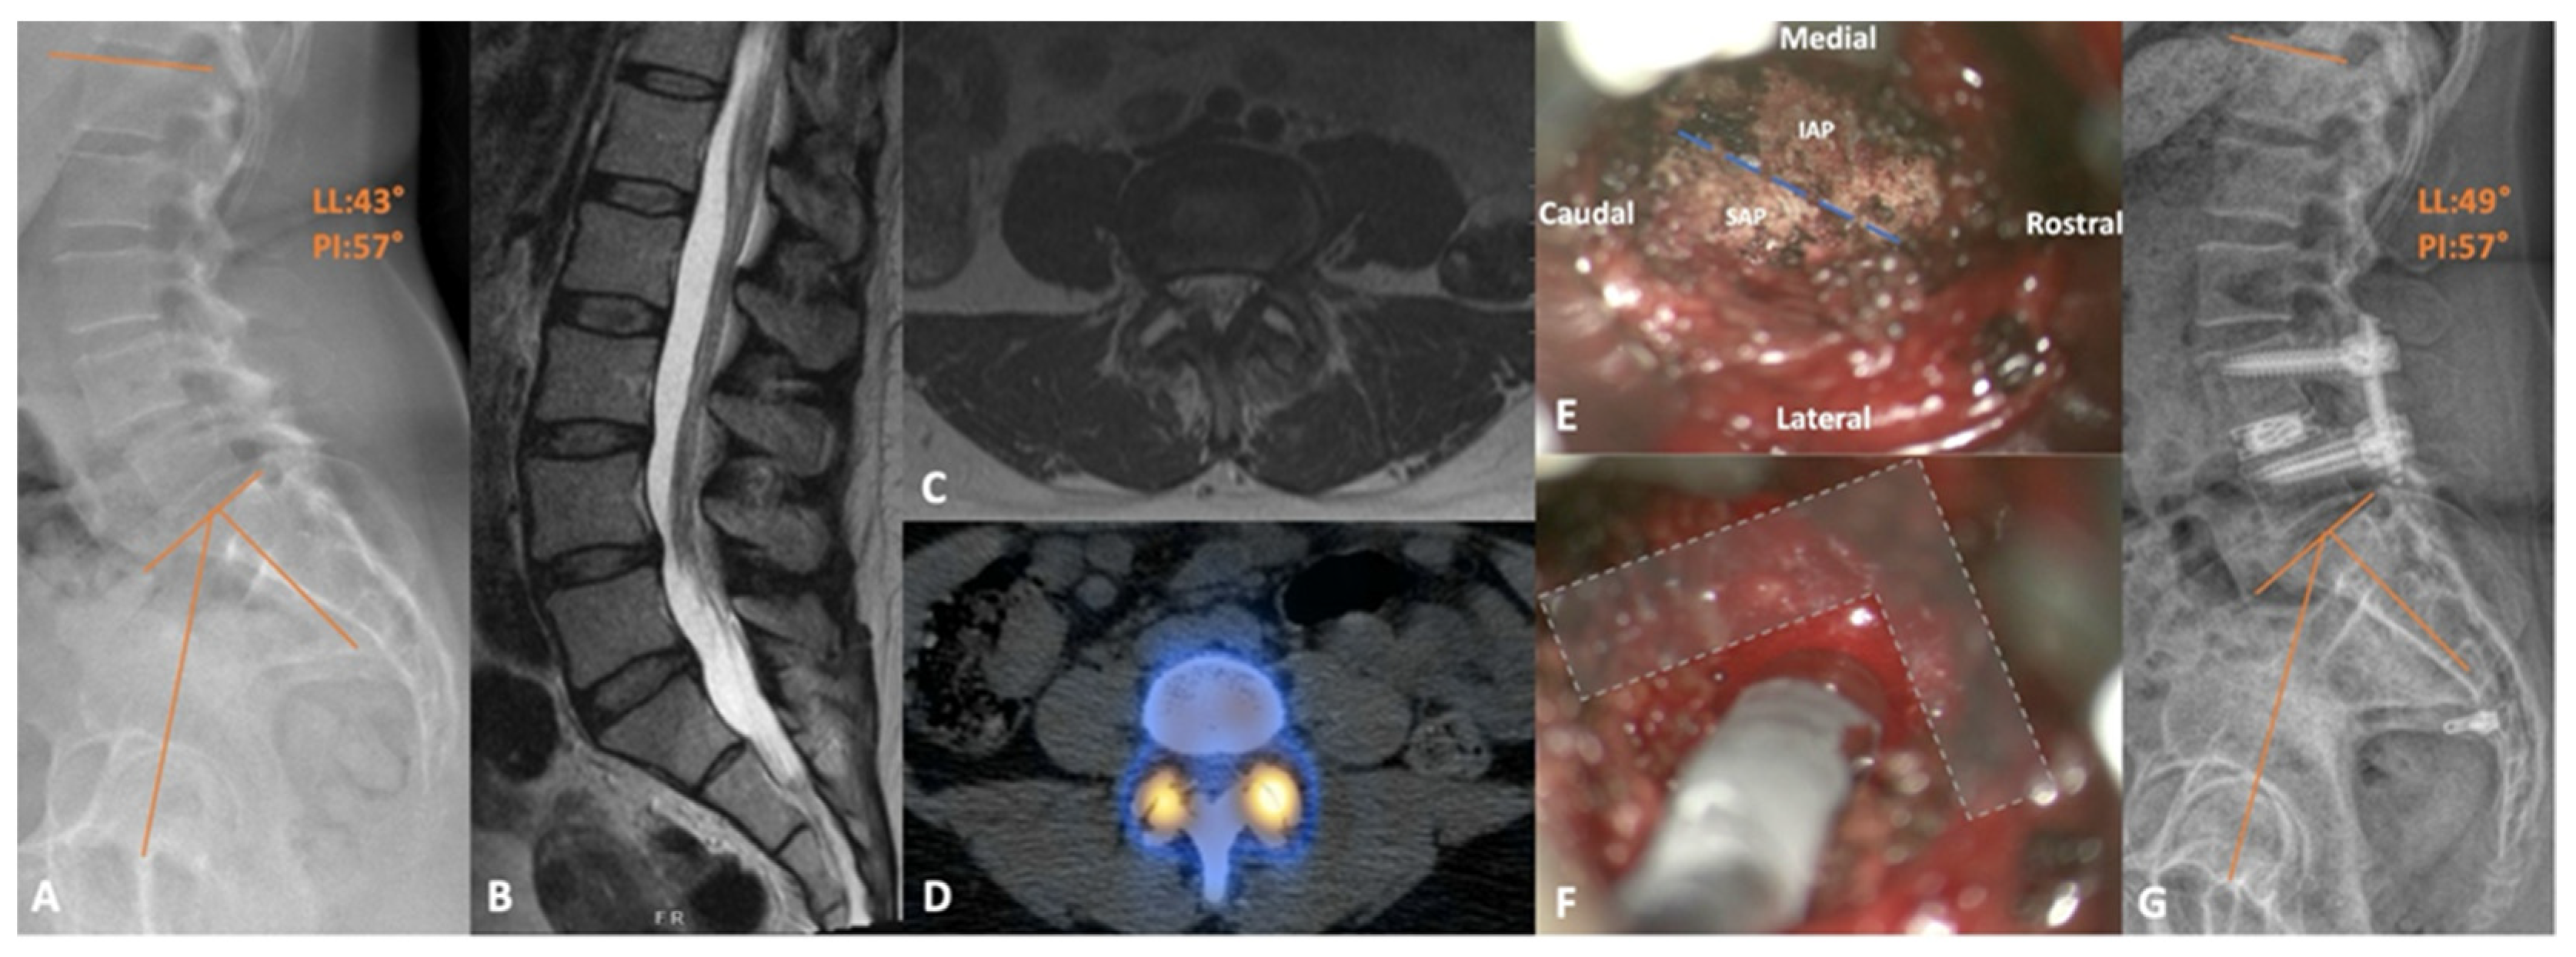

5. Trans-Kambin’s Triangle Lumbar Interbody Fusion

5.1. Percutaneous Endoscopic Transforaminal Lumbar Interbody Fusion

- Tabarestani, T.Q.; Salven, D.S.; Sykes, D.A.W.; Bardeesi, A.M.; Bartlett, A.M.; Wang, T.Y.; Paturu, M.R.; Dibble, C.F.; Shaffrey, C.I.; Ray, W.Z.; et al. Using Novel Segmentation Technology to Define Safe Corridors for Minimally Invasive Posterior Lumbar Interbody Fusion. Oper. Neurosurg. 2023. [Google Scholar] [CrossRef] [PubMed]

- Tabarestani, T.Q.; Sykes, D.A.W.; Kouam, R.W.; Salven, D.S.; Wang, T.Y.; Mehta, V.A.; Shaffrey, C.I.; Wiggins, W.F.; Chi, J.H.; Abd-El-Barr, M.M. Novel Approach to Percutaneous Lumbar Surgeries via Kambin’s Triangle-Radiographic and Surgical Planning Analysis with Nerve Segmentation Technology. World Neurosurg. 2023, 177, e385–e396. [Google Scholar] [CrossRef] [PubMed]

- Tabarestani, T.Q.; Sykes, D.A.W.; Maquoit, G.; Wang, T.Y.; Ayoub, C.M.; Shaffrey, C.I.; Wiggins, W.F.; Abd-El-Barr, M.M. Novel Merging of CT and MRI to Allow for Safe Navigation into Kambin’s Triangle for Percutaneous Lumbar Interbody Fusion-Initial Case Series Investigating Safety and Efficacy. Oper. Neurosurg. 2023, 24, 331–340. [Google Scholar] [CrossRef] [PubMed]